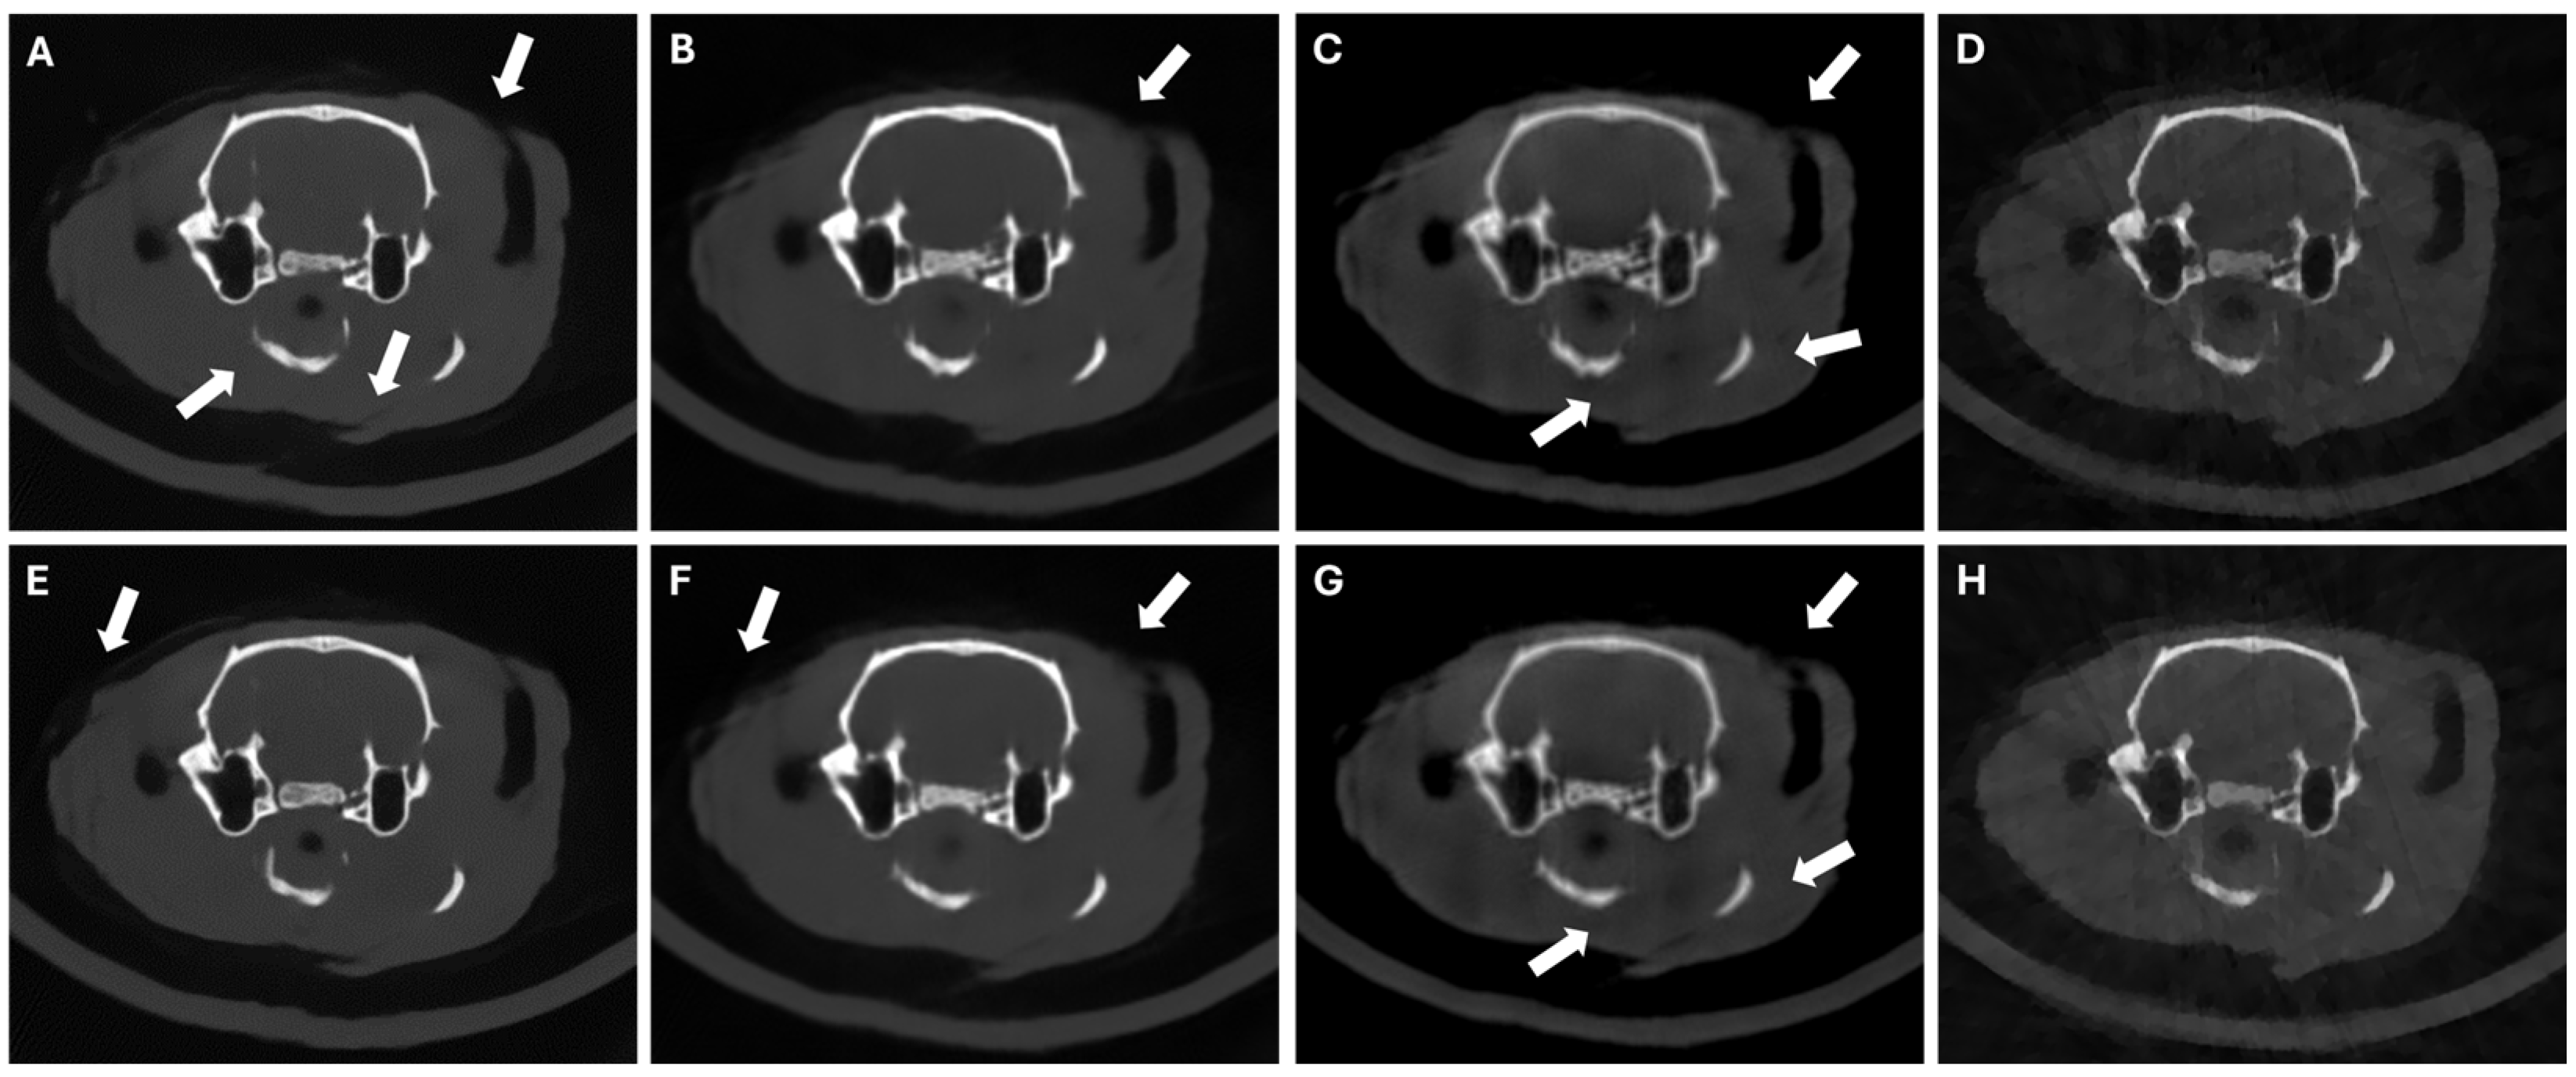

Figure 6 shows that SART-PICCS is sensitive to the hallucinations in the prior image, while PICDL achieves almost identical results for priors obtained with different random seeds, with only minor differences appearing in internal structures with higher intensity, reaching very similar PSNR and SSIM values (Table 3). This demonstrates the robustness of the method against changes in the prior image.

Figure 6.

LNP scenario of 42 random projections with random seed = 42 (top) and random seed = 33 (bottom). Axial slices of DeepBH (A,E), prior images (B,F), SART-PICCS (C,G), and PICDL (D,H). Arrows indicate hallucinations.